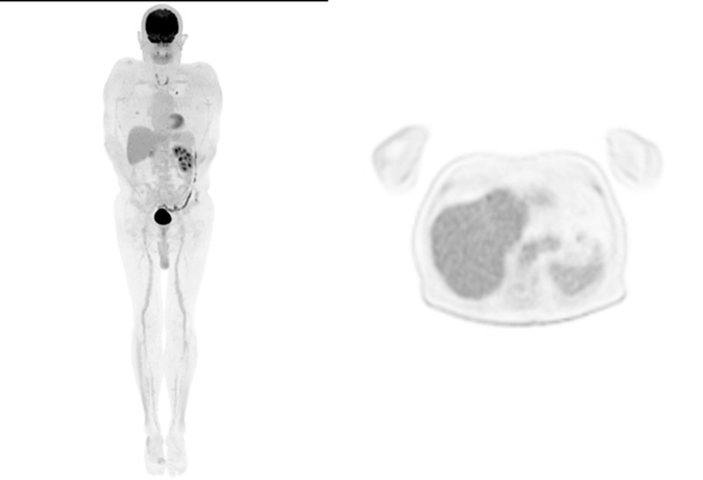

Secondly, in terms of image quality, our team has seen first-hand the major step up from analog to digital cameras and the progressive image improvement with successive iteration of UIH's AI algorithm. This is particularly striking when the same patient returns for their follow-up studies (see Figure 1-3) on the different platforms.

Figure 3. MIP and axial image of patient with metastatic renal cell carcinoma scanned on uMI 780 with latest generation HYPER DPR, AI PET algorithm (injection dose: 244 MBq of 18F-FDG, 60 min uptake time, scan time: 2 min/bed position)

HYPER DLR's algorithm is based on deep learning through artificial neural networks, The algorithm improves signal to noise ratio by up to 50%, allowing shorter acquisition time if required. It is also effective in reducing image noise in patients with high BMI.

HYPER DPR builds on this, further enhancing the signal to noise ratio, accentuating lesion contrast and thus improving small lesion detectability. Compared with other possible AI algorithms, its unique advantage is that its networks were created using United Imaging's uExplorer® data. HYPER DPR claims a 32% improvement on noise reduction, 66% improvement on image contrast and overall 2.5 times improvement on SNR.